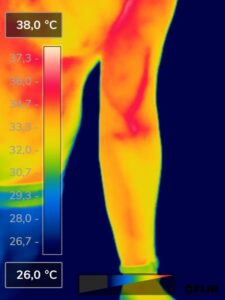

Como na sequência de termogramas abaixo de um paciente do sexo masculino, de 44 anos, sem comorbidades e praticante de atividade física que apresentou fortes dores em braço esquerdo (com irradiação para antebraço) após treino de musculação. Esta dor chegou a ser incapacitante, pois impossibilitava inclusive o paciente a realizar atividades de vida diárias como pegar um copo de água.

Após a realização de uma Análise Termofuncional©®, foi detectado alterações térmicas em “linha”, margeando as fibras musculares e tendíneas inferiores (insercionais) bicipitais. Estas alterações também aventaram a hipótese de dilatação venosa, por alguma reação inflamatória local. Foi realizado então aplicação de laserterapia através da Técnica Termoguiada, que acabou por promover a completa analgesia em 24 horas após aplicação.